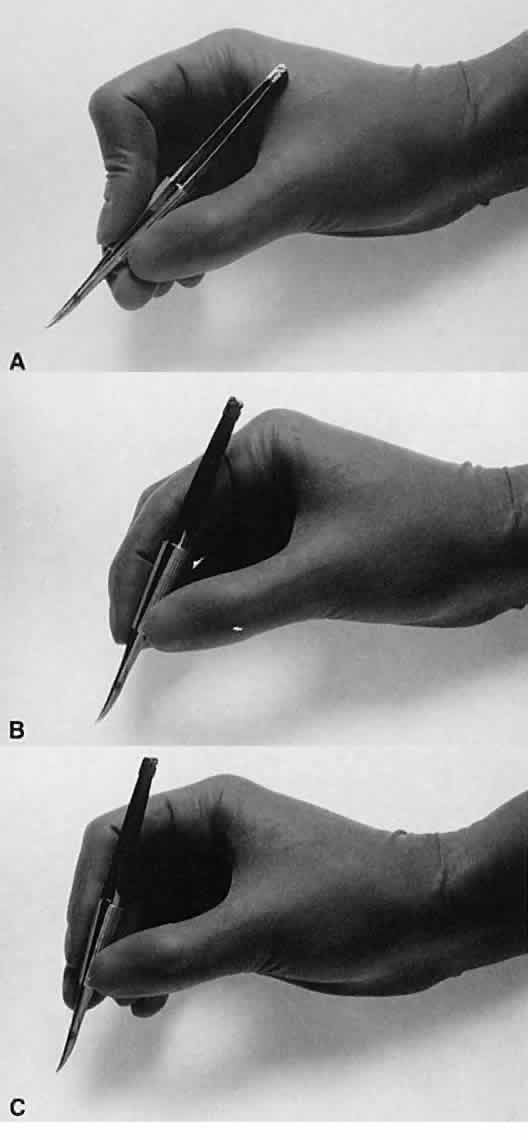

No surgical instruments are intended to be held like a pencil, resting

in the crotch between the thumb and forefinger (Fig. 12).3 In conventional eye surgery, longer instruments usually are rested against

the first metacarpophalangeal joint, with the thumb and first two

fingers encircling the handle. Stability is achieved by resting the side

of the fifth finger on the periorbital facial structures. This method

of holding surgical instruments allows for rotation of the instrument

between the fingertips, by flexing the fingers, or by rotating the

wrist. Great mobility is necessary when using a needle holder (needle

driver) to pass a needle through tissue. When the surgeon encounters

resistance from the tissue, it is usually necessary for the surgeon to

twist the wrist or apply counter pressure on the tissue at the exit site

of the needle. Holding surgical instruments correctly provides the

surgeon with increased flexibility and mobility. The serrations on the

handle, regardless of style, allow the surgeon to hold the instrument

lightly, but firmly. With the level of precision of currently available

instruments, it is never necessary to grasp an instrument tightly. The

tendency to grasp instruments tightly must be avoided because it

decreases flexibility and increases fatigue of the hand and forearm muscles. Any

resistance encountered when placing an instrument into or out

of the eye is secondary to positioning of the instrument. Adjusting

the angle of the instrument or your hands should allow easier placement

of the instrument.  Fig. 12. A. A surgical instrument held like a pencil, resting in the crotch between

the thumb and the forefinger. No surgical instruments are intended to

be held in this manner. B. A longer surgical instrument held resting against the first metacarpophalangeal

joint of the first finger, with the thumb and the first finger

encircling the handle. This position allows for rotation of the instrument

between the fingertips or by flexing the fingers or wrist. C. The surgical instrument is held between the thumb and fingertips of the

second and third digits. This position allows for a more perpendicular

positioning of the instrument on the eye. Fig. 12. A. A surgical instrument held like a pencil, resting in the crotch between

the thumb and the forefinger. No surgical instruments are intended to

be held in this manner. B. A longer surgical instrument held resting against the first metacarpophalangeal

joint of the first finger, with the thumb and the first finger

encircling the handle. This position allows for rotation of the instrument

between the fingertips or by flexing the fingers or wrist. C. The surgical instrument is held between the thumb and fingertips of the

second and third digits. This position allows for a more perpendicular

positioning of the instrument on the eye.